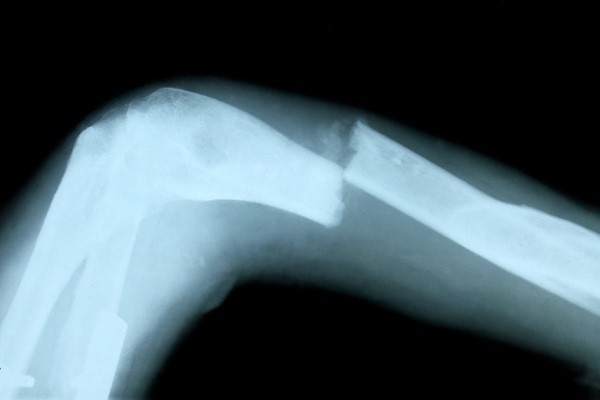

Trung bình mỗi người Mỹ tiêu thụ 104 lít sữa bò mỗi năm, nó và một số nước trong liên minh Châu Âu có tỷ lệ tiêu thụ sữa hàng đầu thế giới, nhưng cũng là các nước có bệnh nhân loãng xương cao nhất.

Nguyên nhân là trong quá trình tiệt trùng sữa, các lợi khuẩn cũng bị tiêu diệt và phá hủy một hàm lượng đáng kể các chất dinh dưỡng trong sữa, như Vitamin C và i ốt, thậm chí cả canxi – một thành phần thiết yếu giúp xương chắc khỏe.

Thế nhưng cơ thể chúng ta hầu như không hấp thụ canxi từ sữa bò, mà nó lại kết hợp với độ pH trong cơ thể để làm mất canxi từ xương chúng ta.

Giống như tất cả protein từ động vật, sữa axit hóa pH của cơ thể và gây ra một sự điều chỉnh sinh học. Bạn biết đấy, canxi là một chất trung hòa axit tuyệt vời và nó được dùng để trung hòa độ axit có trong sữa. Khi canxi bị kéo khỏi xương, nó bị đào thải qua đường nước tiểu do đó dẫn đến tình trạng xương thiếu canxi trầm trọng.